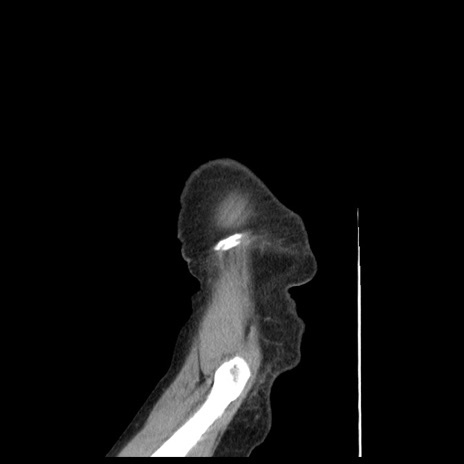

横断像

【症例】80歳代女性

【主訴】腹痛

【現病歴】8時間前から腹痛あり来院。

【既往歴】糖尿病、脂質異常症、子宮体癌にて子宮全摘術

【身体所見】意識清明・会話良好だが腹痛で苦悶様、全腹部にわたって反跳痛と圧痛あり

【データ】WBC 13600、CRP 0.14、LDH 224、CK 90